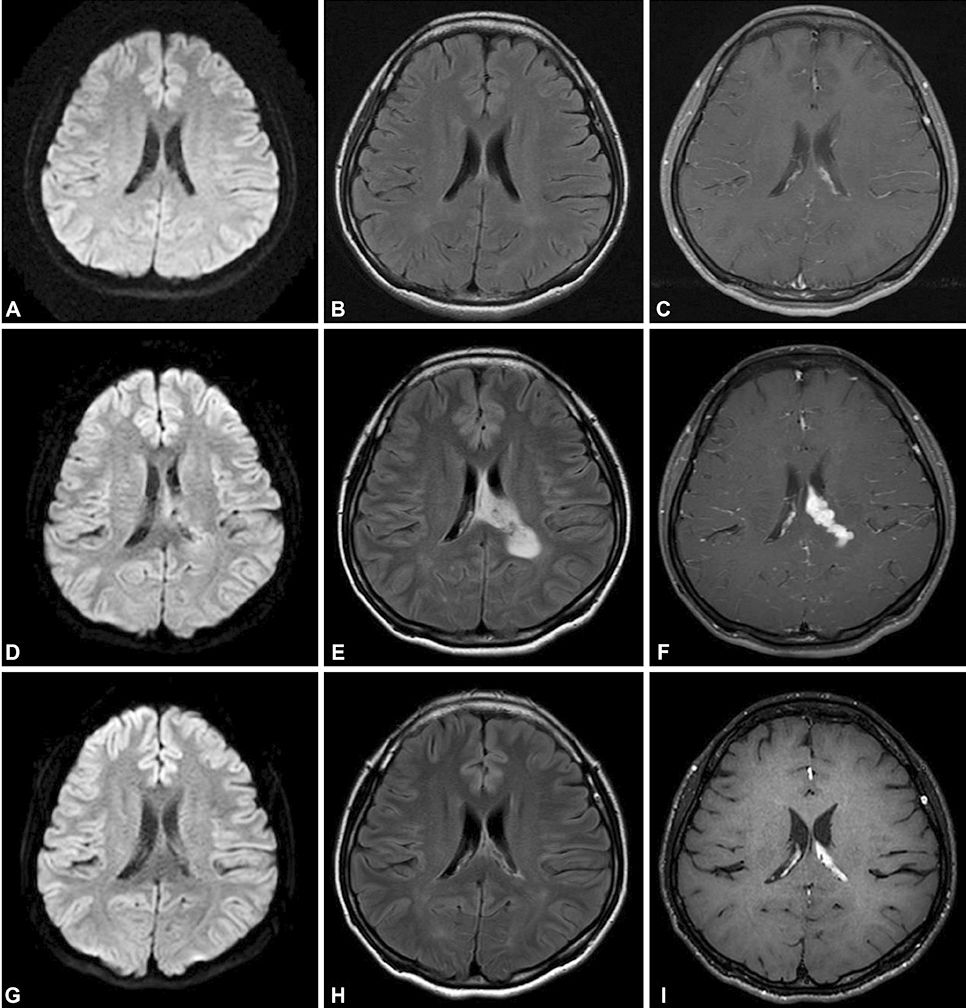

患者30岁,女性,头痛6天。既往类固醇类药物治疗Kikuchi’s 病史,患者入院后胸部CT证实肺结核。脑脊液细菌、分枝杆菌和真菌染色和培养结果均为阴性,但脑脊液结核分枝杆菌聚合酶链反应(PCR)呈阳性,确诊结核性脑膜脑炎。患者在开始使用地塞米松、利福平、乙胺丁醇、异烟肼、吡嗪酰胺和莫西沙星治疗后病情好转。两周后出院,除了轻微头痛,全部症状消失。依次为轴位DWI,FLAIR和钆增强T1加权图像。A-C:初始发病时显示弥漫性软脑膜增强。D-F:抗结核药物治疗后5周出现严重头痛时的随访影像,显示左侧脉络丛炎。G-I:第6个月的随访图像,显示病变明显改善。

答案:矛盾反应。

结核病患者在开始治疗后,临床或放射学上原有病变的恶化或出现了新病变被称为矛盾反应(paradoxical reaction,PXR)。由于PXR可能被误诊为耐药状态或治疗失败,导致结核病的治疗混乱。这个病例的PXR表现为脉络丛炎,在此,期望临床医师提高对这种情况的认识。PXR与宿主免疫应答反应、分枝杆菌产物直接作用有关。

TB得到有效治疗后,结核菌被迅速杀灭后释放大量结核蛋白和胞壁产物,这些蛋白、磷脂、多糖引发超敏反应,出现局部毛细血管扩张、炎性细胞渗出、聚集,进而造成原本不活跃的结核病灶扩大,从而出现相应的临床或影像表现。神经影像学表现包括基底渗出物增加,新发的或恶化的结核瘤以及视神经炎或脊髓炎。渗出严重可以影响阻塞脑脊液回流,导致颅内压升高,以及脊髓疾病,甚至可以以尿潴留为首发症状。矛盾反应危及生命或致残时,需要使用高剂量的糖皮质激素等免疫调节药物治疗。